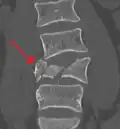

A burst fracture of L4 as seen on plane X ray

A burst fracture of L4 as seen one plane X ray